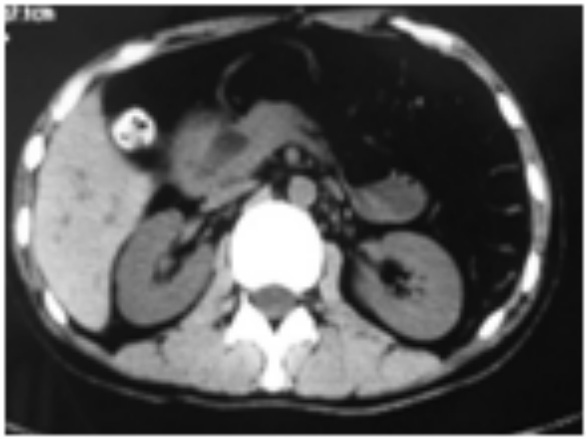

图 1 图中箭头提示胰周积液